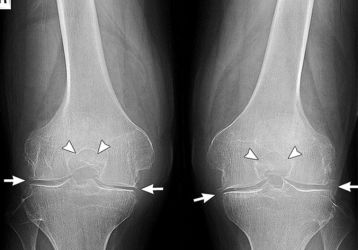

Диета при артрозе коленных суставов: разрешенные и запрещенные продукты

Диета и питание при артрозе коленного сустава: рекомендации по выстраиванию питания, что можно и что нельзя есть при гонартрозе. Список рекомендуемых продуктов.